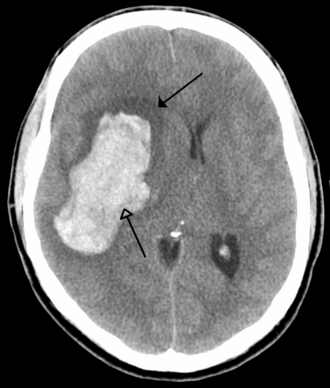

Intracerebralno krvarenje

Obično se javlja u malim arterijama ili arteriolama i najčešće nastaje zbog povišenog krvnog tlaka[24], vaskularnih malformacija središnjeg živčanog sustava (uključujući kavernozne angiome ili arterijskovenske malformacije), cerebralne amiloidne angiopatije ili infarkta u kojima se sekundarno razvilo krvarenje[2]. Drugi potencijalni uzroci su trauma, poremećaji koagulacije, amiloidne angiopatije, komzumiranje droge (npr. amfetamini ili kokain). Hematom se povećava sve dok pritisak okolnog tkiva ne ograniči njegov rast ili ne dođe do dekompresije pražnjenjem u cerebralni ventrikularni sustav, cerebrospinalnu tekućinu ili pialnu površinu. Trećina intrecerebralnog krvarenja je krvarenje u moždane komore. Intracerebralno krvarenje ima smrtnost od 44% nakon 30 dana, višu od ishemijskog moždang udara ili subarahnoidalnog krvarenja (koji e tehnički mogu klasificirati kao vrsta moždanog udara)[2].

Hemoragijski moždani udar rezultira ozljedom tkiva uslijed kompresije tkiva prilikom širenja jednog ili više hematoma. To može narušiti i ozlijediti tkivo. Osim toga, tlak može dovesti do gubitka krvne opskrbe u zahvaćenom području što rezultira infarktom, a krvi otpuštena prilikom moždanog krvarenja čini se da ima izravno toksično djelovanje na moždano tkivo i krvne žile. Upala doprinosi sekundarnom oštećenju nakon krvarenja[15][32] Inflammation contributes to the secondary brain injury after hemorrhage.[32] .